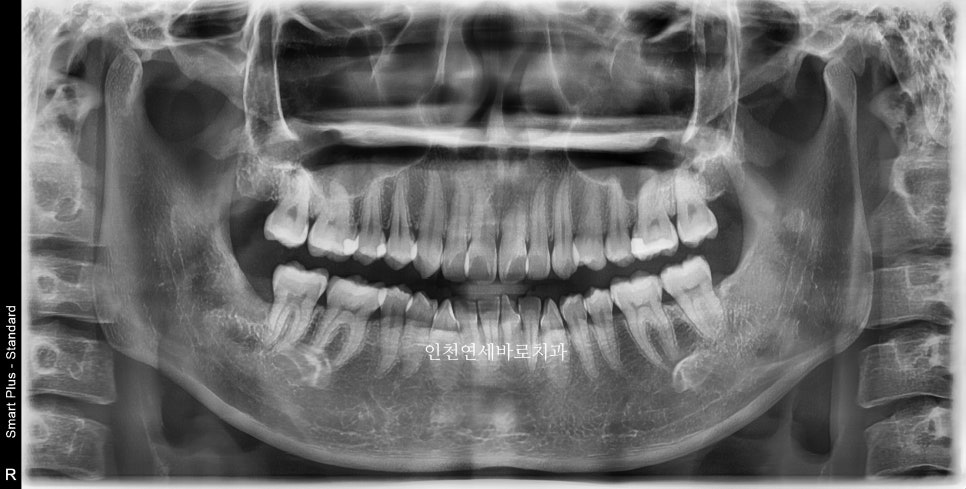

첫 내원 23.12.23.

이후 한달의 제작기간 후 24년 2월초에 시작한 환자분입니다.

삐뚤삐뚤한 앞니를 고치고 싶어오셨습니다

인비절라인 라이트로 진행하기로 하고 장치 제작을 했습니다.